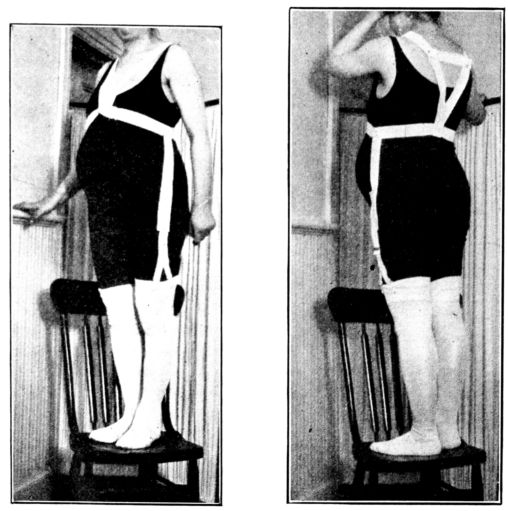

| 34. | Front view of home-made abdominal binder | 123 |

| 35. | Side view of same | 123 |

| 36. | Back view of same | 123 |

| 37. | Abdominal binder used in above | 124 |

| 38. | Front view of home-made stocking supporters | 124 |

| 39. | Back view of same | 124 |